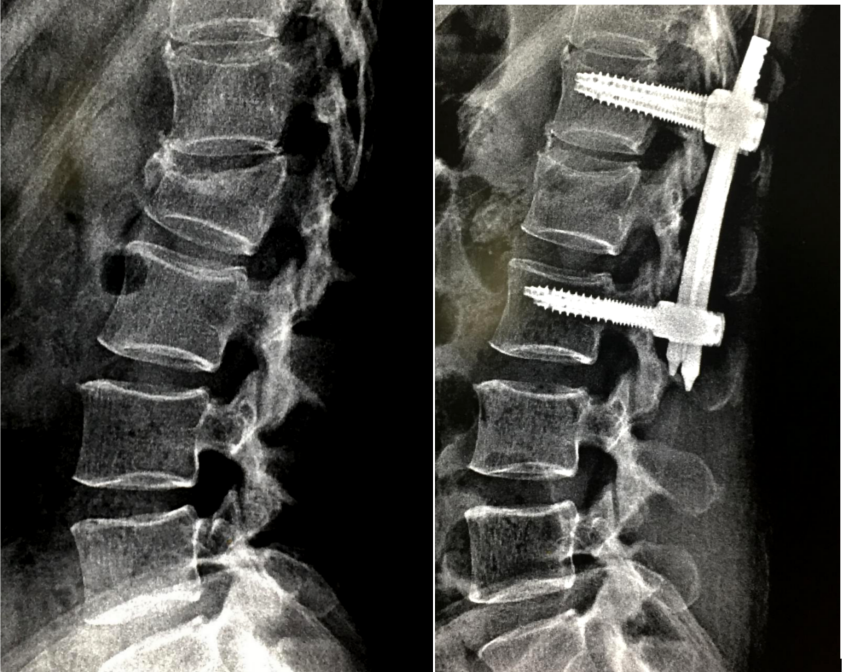

开放手术治疗

对有脊髓及神经压迫症状和体征、严重后凸畸形、需行截骨矫形以及不适合行微创手术的不稳定椎体骨折患者,可考虑行手术治疗。

为提高骨质疏松症患者内固定的稳定性,可选用特殊设计的螺钉,如加长加粗的螺钉、可膨胀螺钉或者带涂层螺钉,提高螺钉的抗拔出力;

采用特殊的置钉技术,如双皮质固定技术、皮质骨轨迹技术增强螺钉的稳定性;

延长固定节段或者使用多点固定,如椎板钩、椎板下钢丝辅助椎弓根螺钉固定可增加内固定强度;

在椎弓根螺钉周围局部注射骨水泥也可有效防止螺钉拔出,但应注意骨水泥渗漏风险和翻修困难等问题。